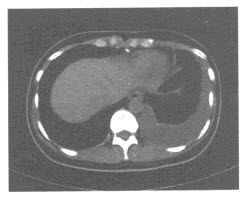

30、单项选择题

男,16岁,大腿可触及柔软、无痛性肿块,结合图像,最可能的诊断是()

A.滑膜肉瘤

B.脂肪肉瘤

C.脂肪瘤

D.血管瘤

E.淋巴管瘤